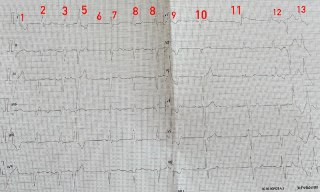

Так виглядає динаміка NSTEMI 1. Біль за грудиною + 2. Зміни на ЕКГ (перше фото: депресія до 1 мм V4-V6, друга плівка н...